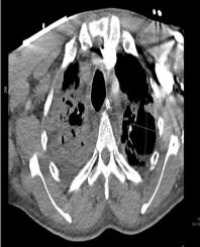

Robot-Assisted Laparoscopic Bladder Neck Reconstruction with Retzius-Sparing Approach for the Treatment of 3 Cases of Refractory Bladder Neck Contracture

We present the preliminary outcomes of robotic-assisted surgical treatment for bladder neck contracture (BNC), using the innovative Robot-Assisted Laparoscopic Retzius-Sparing Bladder Neck Reconstruction (RAL-RSBNR), technique. Between August and October 2024, three adult male patients underwent RAL-RSBNR at our institution. All patients developed BNC following transurethral resection of the prostate (TURP), for benign prostatic hyperplasia (BPH), and had previously undergone multiple urethral dilation procedures. One patient had experienced recurrent TURP interventions. All RAL-RSBNR procedures were performed using a transperitoneal six-port approach with a four-arm robotic system. No significant intraoperative or postoperative complications were observed. At two weeks postoperatively, all three patients successfully had their catheters removed without notable voiding difficulties. Current literature identifies the RAYV technique as the predominant robotic-assisted approach for treating BNC. In contrast, our novel RAL-RSBNR technique addresses BNC at its root, effectively preventing recurrence often associated with endoscopic surgeries, while maintaining a favorable safety profile with no major complications. These preliminary results indicate that RAL-RSBNR holds significant potential as a promising option for BNC treatment. Nevertheless, given the short study period, further clinical data and extended follow-up are required to thoroughly evaluate the long-term outcomes and efficacy of RALRSBNR.